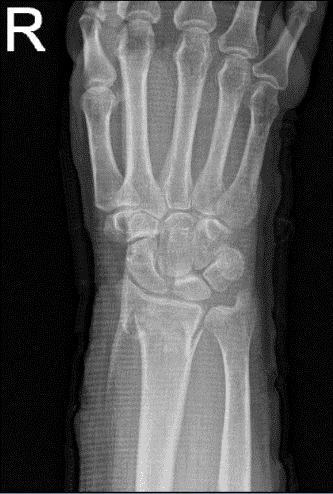

Un paciente de 69 años estaba en nuestra consulta con quejas sobre dolor y deformidad en la muñeca derecha. Allí le pusieron una férula de azúcar y ahora está en Nueva York. Ella sufrió el dolor por la caída. Para los factores agravantes, el paciente informa de empujes/tirones y de carga de peso.

En cuanto a los síntomas asociados, informó de debilidad, hinchazón, sensibilidad al tacto y dolor al moverse, pero no informó entumecimiento, hormigueo, enrojecimiento, calor, equimosis, bloqueo/atrapamiento, chasquido, pandeo, rechinación, inestabilidad, radioterapia, drenaje, fiebre, escalofríos, pérdida de peso y cambios en los hábitos intestinales o urinarios.

El paciente presentó un resultado de resonancia magnética que contenía fractura de Colles con angulación dorsal.

Radiografía de la muñeca derecha 3 o más vistas